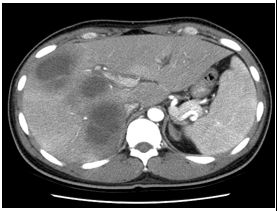

11. 27歲男性,過去身體健康良好,並無抽菸、酗酒或動物接觸史,因為二週來發燒、逐漸氣促(dyspnea)、吞嚥困難和體重減輕10公斤,來院求醫。理學檢查發現病患意識清楚,體溫攝氏38.5度,血壓120/78 mmHg,脈搏每分鐘116次,呼吸每分鐘28次。口腔內有白色斑塊,胸部理學檢查並無特別發現。胸部X-光如圖A所示。支氣管鏡檢切片的病理檢查如圖B所示。請問最有可能的病和治療配對為何? (A) Pneumocystis jirovecii-- Trimethoprim-sulfamethoxazole (B) Legionella pneumophila-- Levofloxacin (C) Cryptococcus neoformans-- Fluconazole (D) Influenza-- Oseltamivir (E) Streptococcus pneumoniae-- Azithromycin